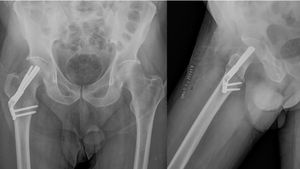

The Femoral Neck System (FNS) (DePuy Synthes®) is an alternative osteosynthesis method for subcapital hip fractures (Fig. 1). Although it has demonstrated mechanical superiority over traditional implants in anatomical studies, it is crucial to evaluate the safety and establish the patient outcomes of this new implant. Few studies analyse clinical outcomes to determine whether it is a superior alternative to CT for the management of non-displaced subcapital hip fractures in adults.8–10

For patients in the FNS group, an antirotation Kirschner wire was first placed to maintain fracture reduction. The wire was positioned as superior and lateral as possible to the centre of the femoral neck to avoid interfering with the placement of the initial FNS pin. A guide wire was then inserted towards the femoral neck with the assistance of a guide device, centering it in the femoral neck. After achieving a satisfactory position, the FNS pin was placed. Once the lateral femoral plate was correctly positioned, two metaphyseal locking screws were inserted after performing the guided drill holes. Finally, an antirotation screw of the appropriate length was inserted. The position of the FNS was confirmed by fluoroscopy, and the anti-rotation K-wire was removed after confirming its correct position (Fig. 2).